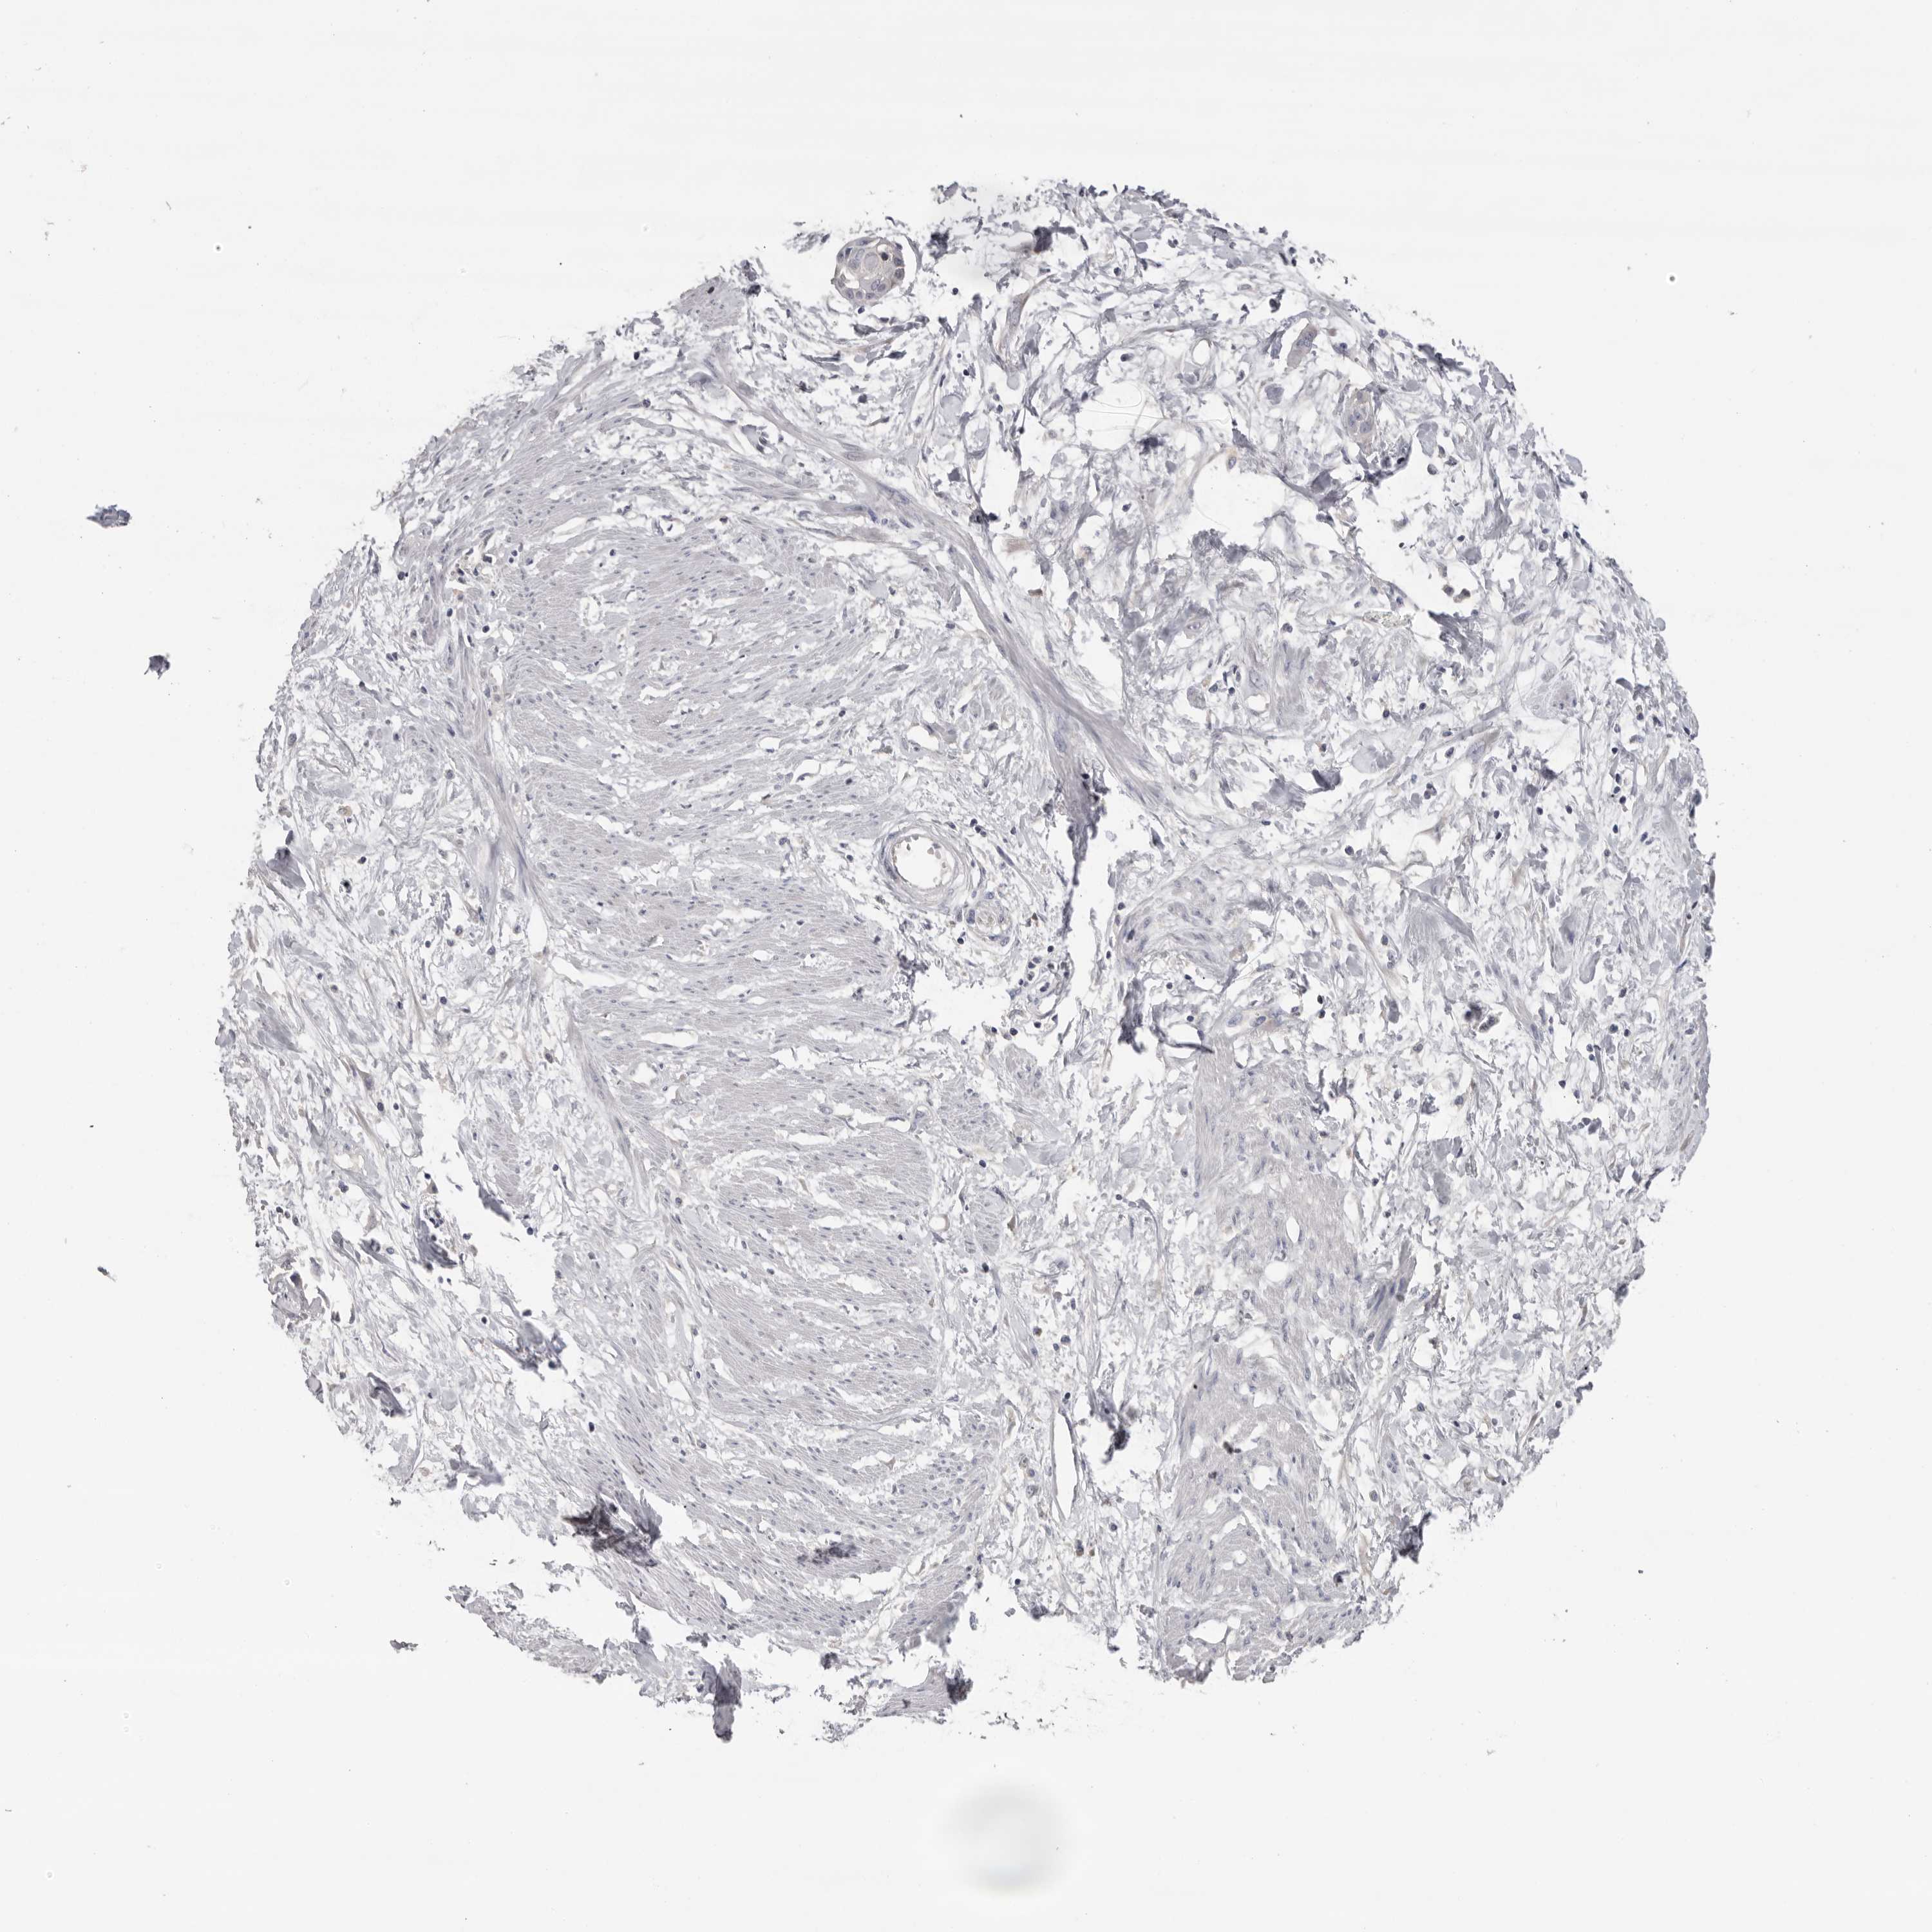

CERVICAL CANCER - Protein expressioni

A mouse-over function shows sample information and annotation data. Click on an image to view it in a full screen mode. Samples can be filtered based on level of antibody staining by selecting one or several of the following categories: high, medium, low and not detected. The assay and annotation is described here.

Note that samples used for immunohistochemistry by the Human Protein Atlas do not correspond to samples in the TCGA dataset.

Antibody stainingi

Antibody staining in the annotated cell types in the current human tissue is reported as not detected, low, medium, or high, based on conventional immunohistochemistry profiling in selected tissues. This score is based on the combination of the staining intensity and fraction of stained cells.

Each image is clickable and will lead to virtual microscopy that enables deeper exploration of all samples and also displays staining intensity scores, fraction scores and subcellular localization as well as patient and tissue information for each sample.

Antibody HPA023081

Squamous cell carcinoma, NOS